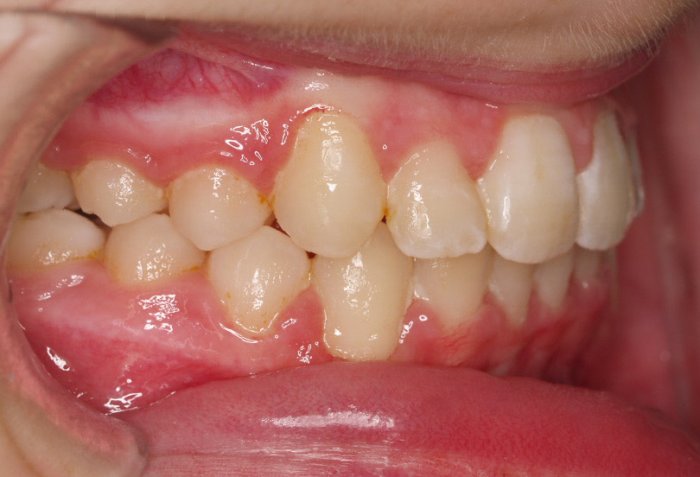

El paciente A.J. de 11 años, acude a nuestra consulta con apiñamiento maxilar importante. El canino lateral (12) está en mordida cruzada. Presenta una Clase II molar y canina, y la línea media está desviada. Se realizó un tratamiento con brackets autoligables metálicos de smartclip 022. La duración del tratamiento fue de 22 meses.